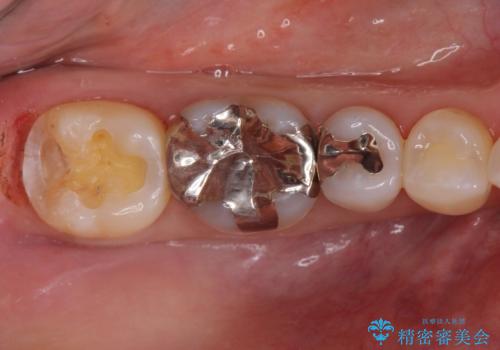

歯ぐきの形を整えることで精度の良い詰め物を入れることができました。

- 右下7 ゴールドインレー 77,000円費用は治療当時の料金となります